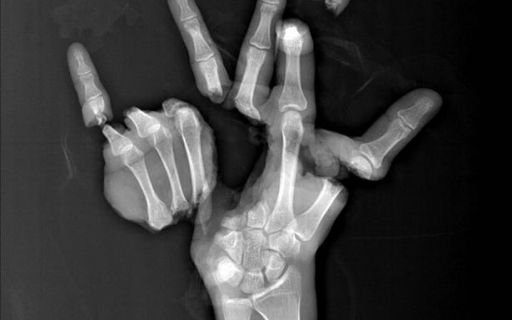

Врач "сшил" руку обратно в одно целое после того, как она была полностью повреждена в дробильной машине